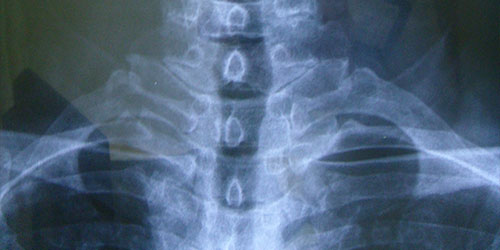

病例二

徐**,男性,于2006年2月24日因第3/4颈椎椎间盘突出症,颈椎前路椎间盘切除,同种异体骨椎体间植骨融合内固定手术,术后2个月,11个月及4年半随访植骨块愈合良好